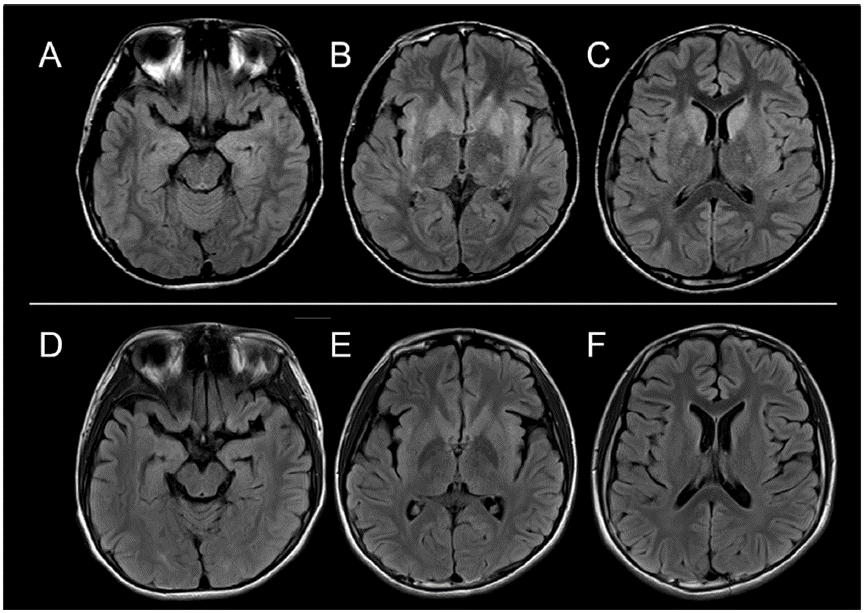

其他檢查包括血清去甲腎上腺素水平顯著降低(0.03 ng/ml;正常范圍 > 0.10 ng/ml)、123I-MIBG心肌顯像示心臟/縱隔比值正常、外周運(yùn)動和感覺神經(jīng)傳導(dǎo)檢查無異常。發(fā)病2周后行頭顱MRI檢查,發(fā)現(xiàn)雙側(cè)尾狀核、殼核、海馬、島葉皮質(zhì)高信號(圖1 A-C)。單光子發(fā)射計算機(jī)斷層顯像(SPECT)腦血流評估示左側(cè)額顳區(qū)攝取減低,苯二氮卓受體顯像示左側(cè)額區(qū)攝取減低。

圖1 癥狀發(fā)作后2周,MR軸位液體衰減反轉(zhuǎn)恢復(fù)序列顯示雙側(cè)尾狀核、殼核、海馬和島葉皮質(zhì)高信號。這些異常強(qiáng)度在癥狀發(fā)作(DF)后3周減弱。

重復(fù)免疫調(diào)節(jié)治療(IVIg 2次,IVMP 4次,潑尼松龍共4個月)后痊愈。痊愈后1個月時患者可獨(dú)立說話、行走和進(jìn)食。3周后復(fù)查頭顱MRI,未見異常(圖1 D-F)。2個月時,腦電圖、SPECT和血清兒茶酚胺水平恢復(fù)正常,頭部18F FDG-PET結(jié)果正常。全身增強(qiáng)CT及18F FDG-PET均未見癌癥病變。在發(fā)病后3個月,患者出院時僅出現(xiàn)輕度體位性低血壓。